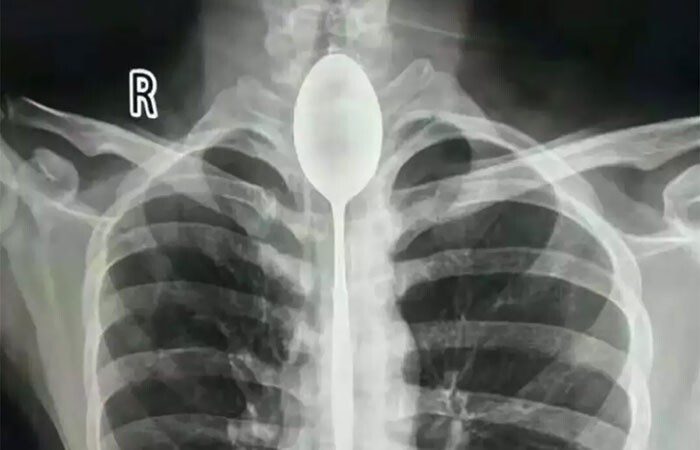

Китаец целый год проходил с ложкой в пищеводе. Удивительно, но ему это не доставляло неудобств